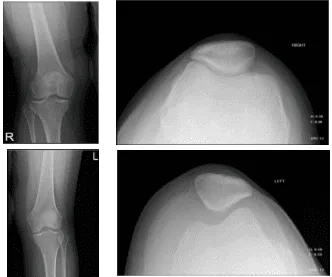

Para el momento, informó del tiempo crónico y nocturno. Para aliviar los factores, hielo y descanso. En cirugías anteriores, ninguna. En las inyecciones anteriores, supuestamente ayudó un poco. El paciente presentó resultados de radiografías que mostraron un pequeño derrame en la articulación de la rodilla derecha. Radiografías de rodilla derecha sin mucho recuerdo.

Radiografía de rodilla con rótula